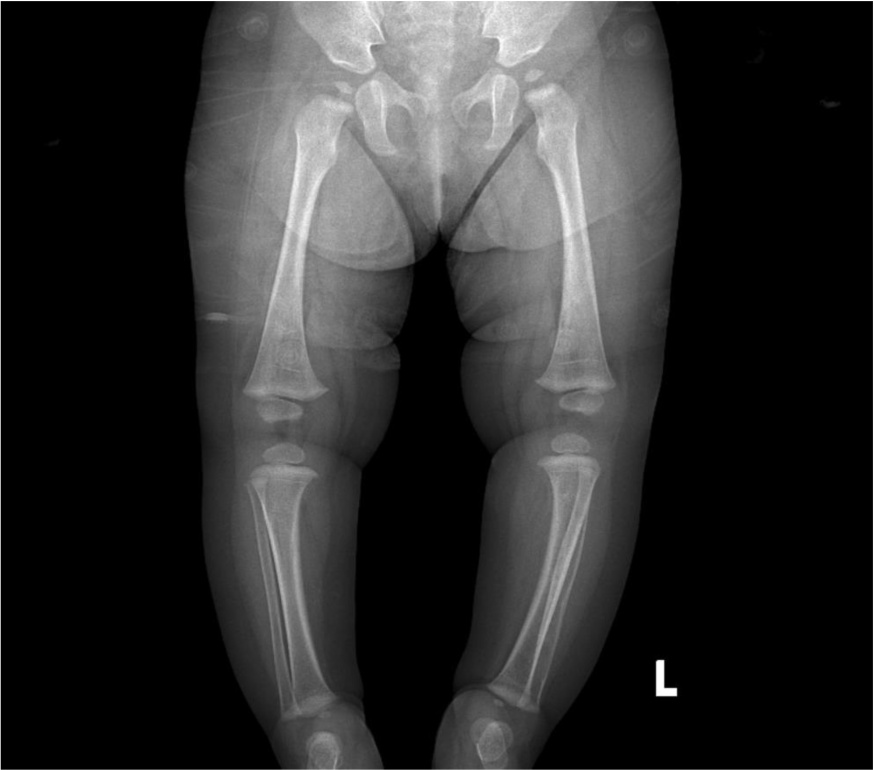

(5) 入院后完善相关检查:2025-09-10,CRP+血常规:C反应蛋白21.43 (mg/L)↑,白细胞计数13.24 (×10^9/L),中性粒细胞计数4.62 (×10^9/L),淋巴细胞计数7.39 (×10^9/L),红细胞计数3.96 (×10^12/L),血红蛋白95 (g/L)↓,血小板计数546 (×10^9/L);2025-09-22,CRP+血常规:C反应蛋白43.80 (mg/L)↑,白细胞计数11.24 (×10^9/L),中性粒细胞计数4.17 (×10^9/L),淋巴细胞计数6.23 (×10^9/L),红细胞计数3.56 (×10^12/L),血红蛋白82 (g/L)↓,血小板计数627 (×10^9/L)↑;2025-09-17,细胞因子:白介素6 29.66 (pg/ml)↑,白介素102.62 (pg/ml)↑,干扰素γ 23.76 (pg/ml)↑;2025-09-23,红细胞沉降率76 (mm/h)↑;大小便常规、降钙素原无异常;肝肾功能、电解质、血糖、血脂、心肌酶谱、凝血功能、免疫功能、风湿全套、狼疮全套大致正常,贫血三项:铁蛋白244.06 (ng/mL)↑;病原学检查:尿培养、痰涂片、输血前、血培养、未见异常。2025-09-16,病原体高通量测序基因检测:人类疱疹病毒5型(CMV)序列数(1993)相对丰度(86.5%);2025-09-10上呼吸道六项病原核酸检测:入院时阴性,住院期间(2025-09-16)呼吸道合胞病毒,阳性(+)↑。影像学检查:2025-09-12,左胫腓骨磁共振(如图2):左侧腓骨髓腔长段囊腔样扩展,髓腔内可见异常强化,骨皮质菲薄,骨膜层状反应性环状增生增厚,骨质破坏不明显,周围软组织明显肿胀、无脓肿及坏死灶形成。2025-09-17,胸部正位片(如图3) + 右股骨正位片和右胫腓骨正位片(如图4):右肩胛骨重叠区、右股骨远端、右胫骨上段低密度影,性质待定,建议进一步检查。2025-09-23,颌面部磁共振(如图5):下颌骨左侧部骨皮质明显不规则增厚,边缘模糊、毛糙,呈T1W1、T2W1低信号,临近软组织肿胀呈明显T2W1高信号。腹部超声未见异常。病理检查:2025-09-15,免疫组化:(左侧小腿软组织)送检肌组织,肌间可见少许淋巴细胞、嗜酸性粒细胞及中性粒细胞浸润,多切片未见恶性证据,请结合临床综合考虑。免疫组化IHC: A01: CK (pan) (−),CD207 (−),CD20 (少量B细胞+),CD1a (−),S-100 (−),Ki67 (+, 约10%),CD3 (少量T细胞+),TdT (−),CD34 (血管+),MPO (少量+),SMA (−)。原位杂交:EBER (−)。基因检查:GATA2 (chr3: 128200145)杂合变异;EXT2 (chr11: 44219362)杂合变异。

Figure 4. Right tibia fibula AP X-ray

4. 右侧下肢正位片

右侧股骨远端和胫骨上端可见类圆形低密度影,大小约分别为10 mm × 9 mm、8 mm × 4 mm,余右胫腓骨骨质连续、完整,未见骨质破坏征象,软组织肿胀。